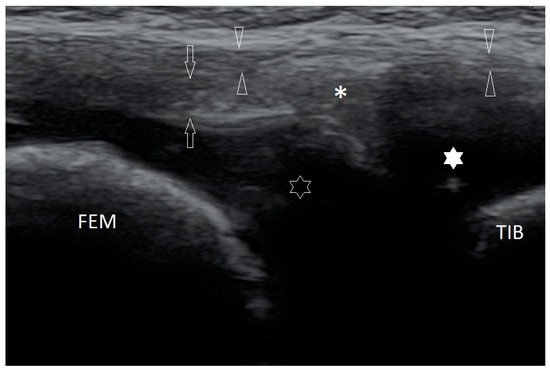

3.2.3. Ligament Injuries

3.2.4. Exfoliation of Growth Plates

3.2.6. Exudates and Inflammations Affecting Joints

3.2.7. Baker’s Cysts